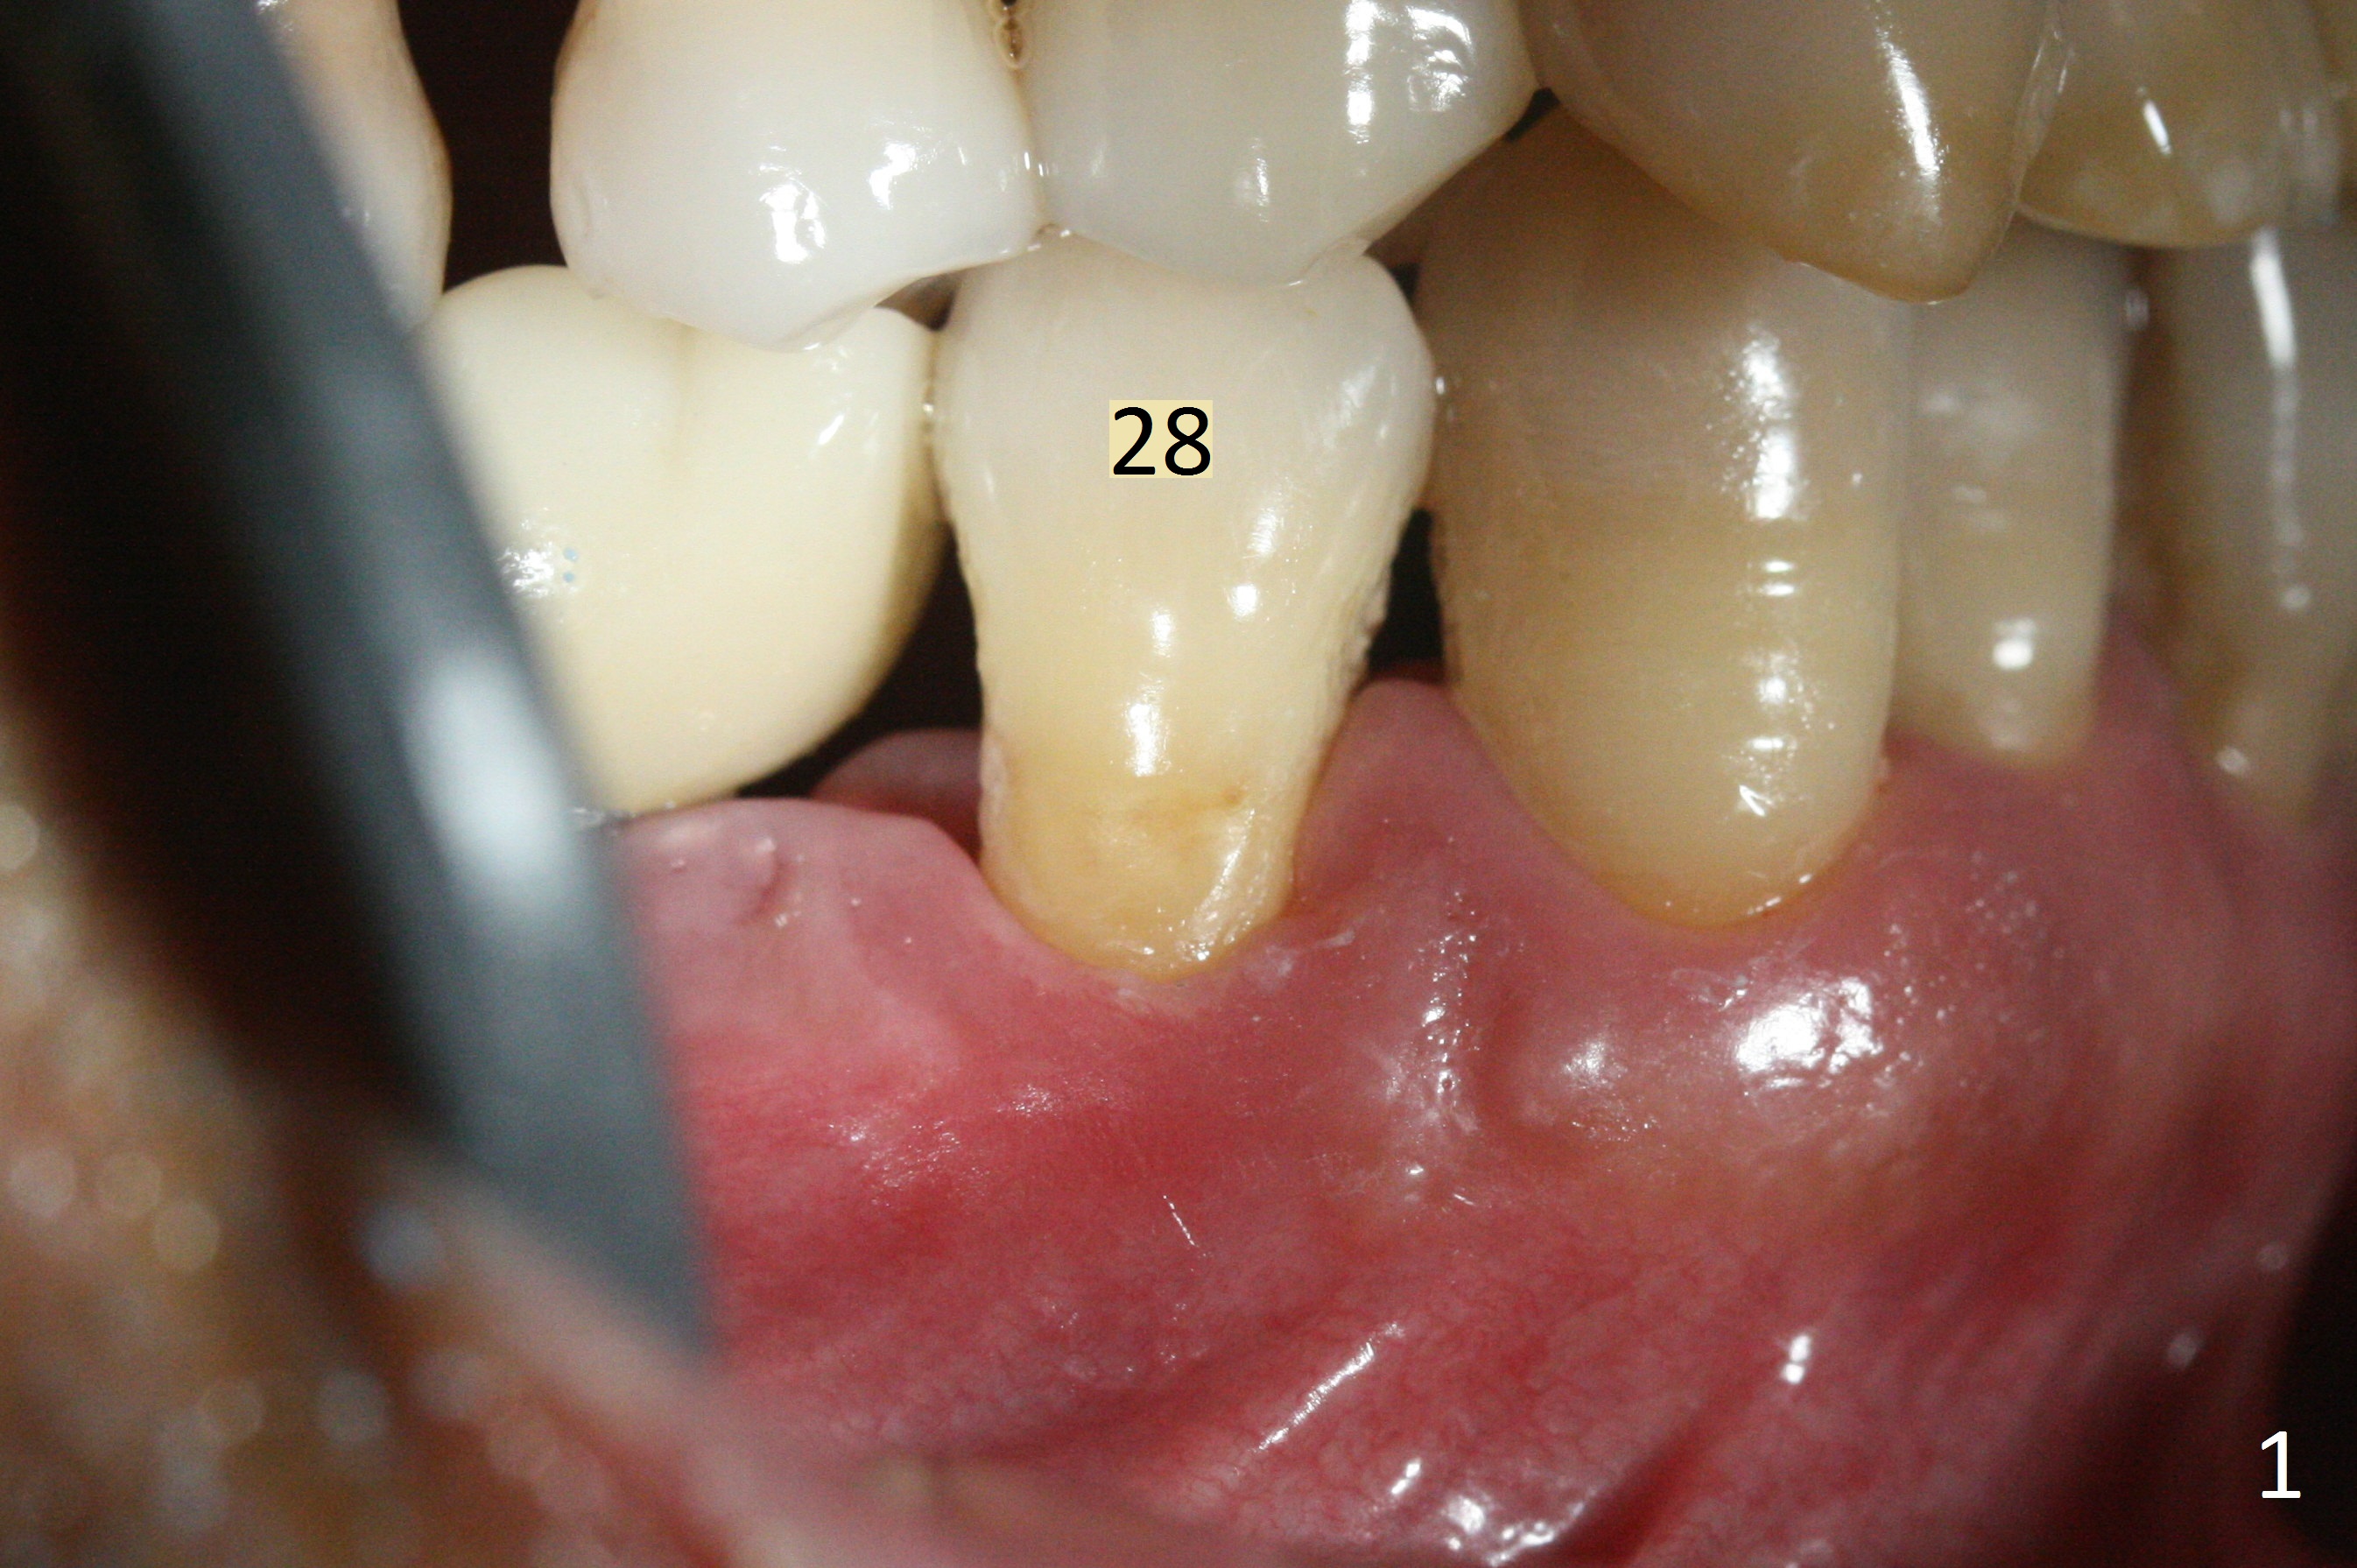

The affected tooth (#28) has buccal gingival recession (Fig.1). As expected, the buccal plate is found low after extraction. Osteotomy is established in the lingual slope of the socket with 1.5 mm drill for 13 mm (Fig.2,3). Following use of Magic Drill 3.3 mm for 13 mm, a 4x11 mm dummy implant is incompletely seated (Fig.4); it is also close to the Mental Loop (Fig.4 red line). After use of Final Drill, a 4x9 mm IBS implant is placed 4 mm and 2 mm subgingival buccal and lingual, respectively (Fig.5) with a large buccal gap (Fig.6 (40 Ncm)). After placement of allograft in the peri-implant space (Fig.7 *), a 4.5x5.7(4) mm abutment is placed (A). A piece of gauze is placed in the remaining buccal space prior to provisional fabrication (Fig.8 *). The space occupied by the gauze is later filled with collagen plug before provisional seating. The gingiva is healthy around the provisional 12 days postop (Fig.9). To reduce buccal gingival recession, the buccal margin of the provisional is shortened 4.5 months postop (Fig.10 arrow). PA taken 5.5 months postop is shown with the implant at 31. The lingual gingiva is erythematous, edematous, and recessive with +BOP and deep pockets 14 months postop (Fig.11). It appears that the small and short implant is not favorable for healing. The infected implant is removed with the missing buccal plate; bone graft is placed 15 months postop (7 months post cementation, Fig.12,13).